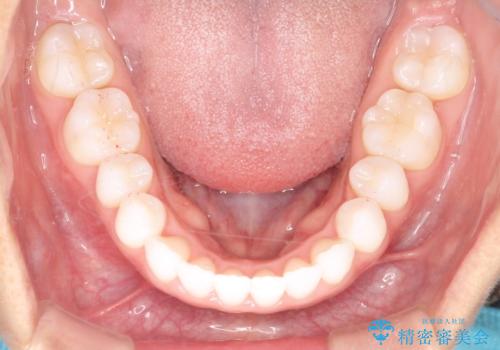

気になる前歯の歯並びをインビザラインで矯正

- 前歯の傾きと、ガタガタが気になるとのことで来院されました。

前歯の傾きや高さをシミュレーションで患者様と確認しながら、歯並びを仕上げていきました。

遠方での合宿などで長期に来院できない場合も、インビザラインなら治療が可能となります。